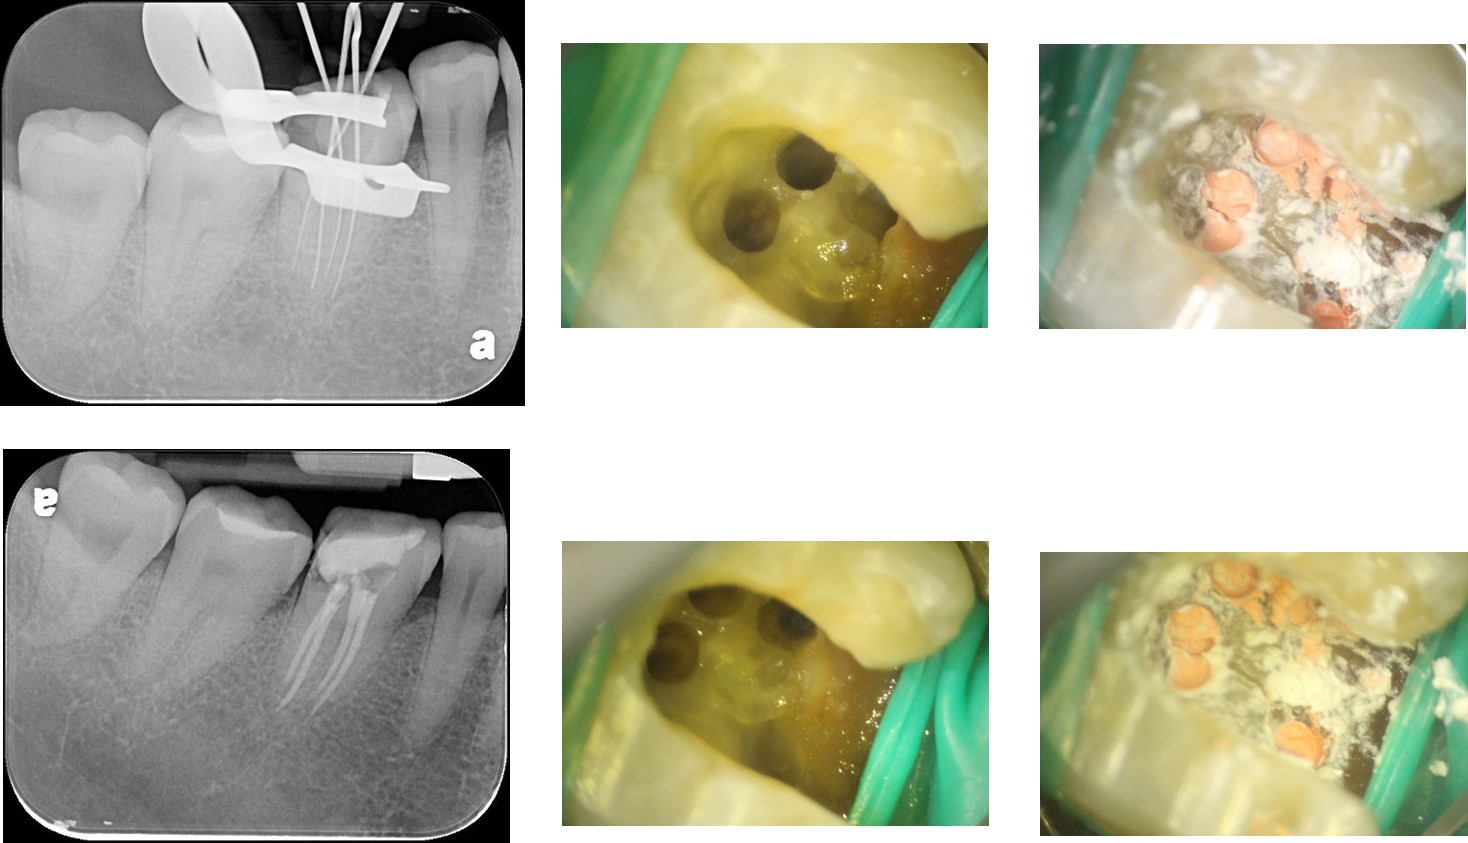

顯微根管治療

鑄造金屬釘柱